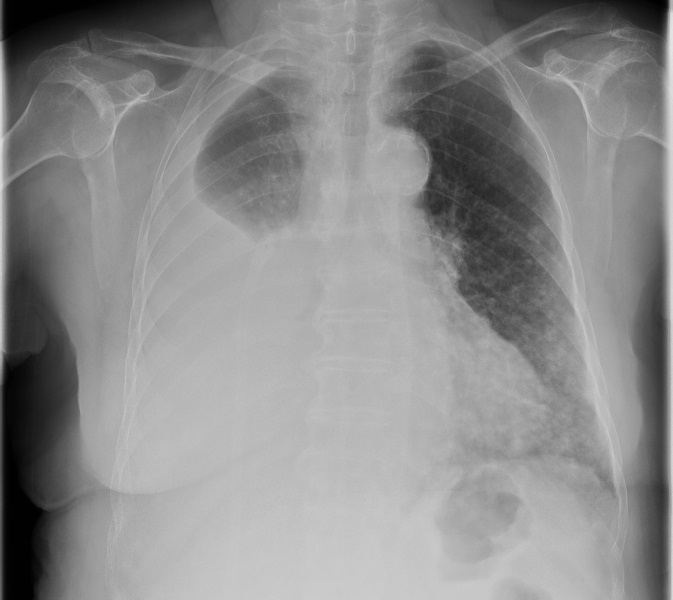

Mme K. est admise aux urgences pour exploration d’une douleur thoracique. Cette femme de 76 ans est suivie en cardiologie depuis dix ans pour un rétrécissement aortique, une hypertension artérielle (HTA) et une dyslipidémie. Elle est parfaitement autonome à domicile. Elle fume un demi-paquet de cigarettes par jour depuis trente ans. Elle est traitée par rivaroxaban (anti-Xa) depuis six semaines pour une thrombose veineuse profonde (TVP) du membre inférieur droit survenue à l’occasion d’un voyage en voiture. Le reste de son traitement comporte de la simvastatine et de l’hydrochlorothiazide.

Depuis trois jours, elle présente une douleur thoracique croissante, latéralisée à droite et survenue sans facteur déclenchant évident.

À évoquer devant une douleur thoracique latéralisée.

À évoquer devant une douleur thoracique latéralisée chez une patiente avec tabagisme important.